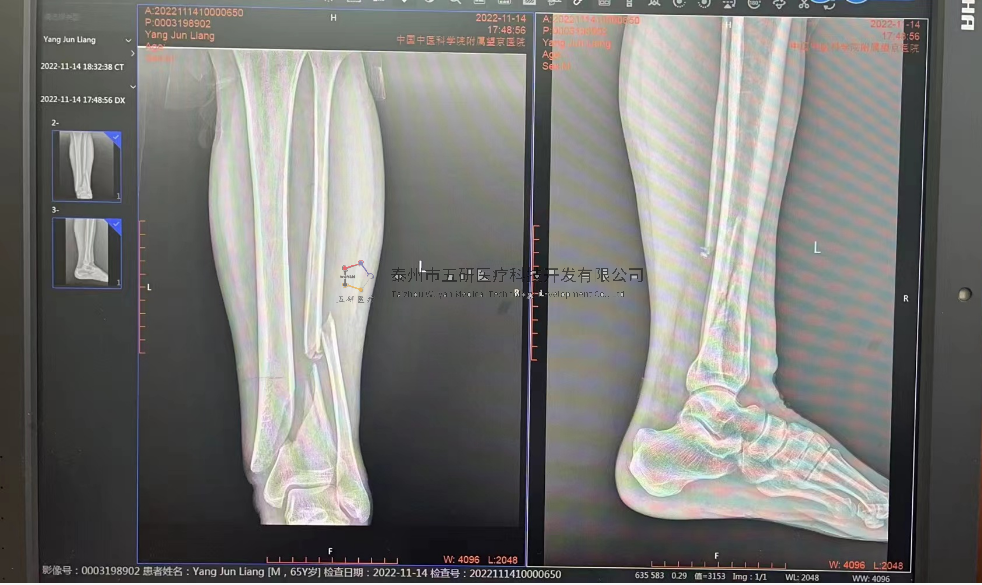

【基本資料】患者,女,61歲

本病例腕架骨折。術前正側位片:右橈骨遠端骨折。